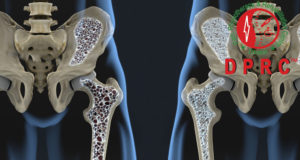

Read More »হাড় ছিদ্র রোগ বা অস্টিওপোরোসিস (Osteoporosis)

মানুষের শরীরে ২০৬ খানা হাড় বা অস্থি থাকে। স্বাভাবিক গঠনে হাড়ে আমিষ, কোলাজেন, ক্যালশিয়াম ও ফসফেট থাকে বলে হাড়ে শক্তিশালী ...